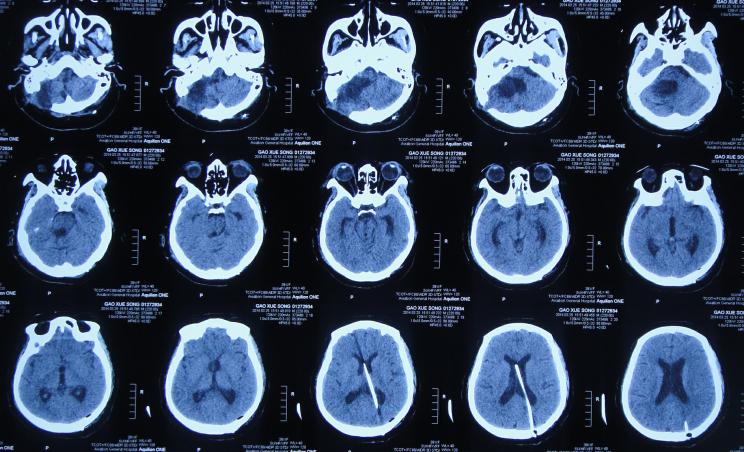

听神经瘤切除术后7天即2013年11月21日,查头颅CT示仍有血肿(图-3),出现发热,最高体温体温38.3 ℃左右,给予腰穿检查脑脊液后认为有感染,给予腰大池引流术及鞘内注射万古霉素。

图-3:2013年11月21日头颅CT